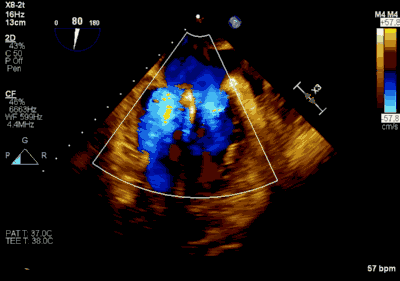

患者全麻以后,在经食道超声心动图和X射线引导下,经股静脉入路,将MitraClip瓣膜夹顺利送至二尖瓣前后叶交界中心处,成功捕捉二尖瓣前叶A2和后叶P2,经超声心动图反复确认瓣叶夹持牢固后,测定有效夹持长度10.4mm,评估反流量降至轻度,释放瓣膜夹,超声心动图评估瓣膜夹位置和功能良好,测定左房压降至26/12mmHg,再次评估反流量仍为轻度,手术顺利完成。

▲ 术后超声检查显示轻度二尖瓣反流